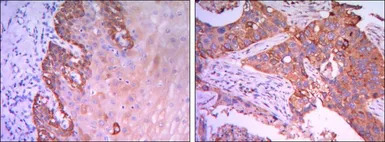

IHC-P analysis of esophagus tissue (left) and human lung cancer (right) using GTX82785 Rab25 antibody [3F12].